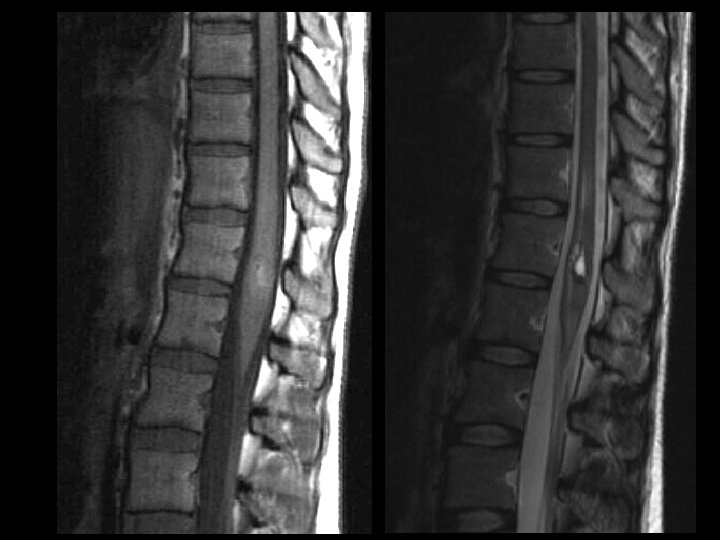

Synovial Cyst of the Lumbar Spine • • • Findings: – Low T 1, high T 2 extradural lesion contiguous with the facet joint – Surrounding enhancement – Mass effect Associated with degenerated joints – 75% at L 4 -5 Typically posterolateral Contents variable – clear fluid, calcium, hemorrhage ddx: – Migrated herniated disc – Perineural cyst (close to nerve root) – Schwannoma (low sig capsule) – Hematoma

Cavernoma of the Spine • • • Findings: – “popcorn-like” intramedullary lesion in the conus – T 2: faint high signal – T 2: high signal centrally, dark rim, and high signal peripherally a. k. a. Cavernoma, cavernous hemangioma, and capillary hemangioma Congenital abnormal cluster of capillaries and venules that periodically bleed Signal characteristics are that of blood in different stages Angiographically occult Look for multiple lesions on GRE